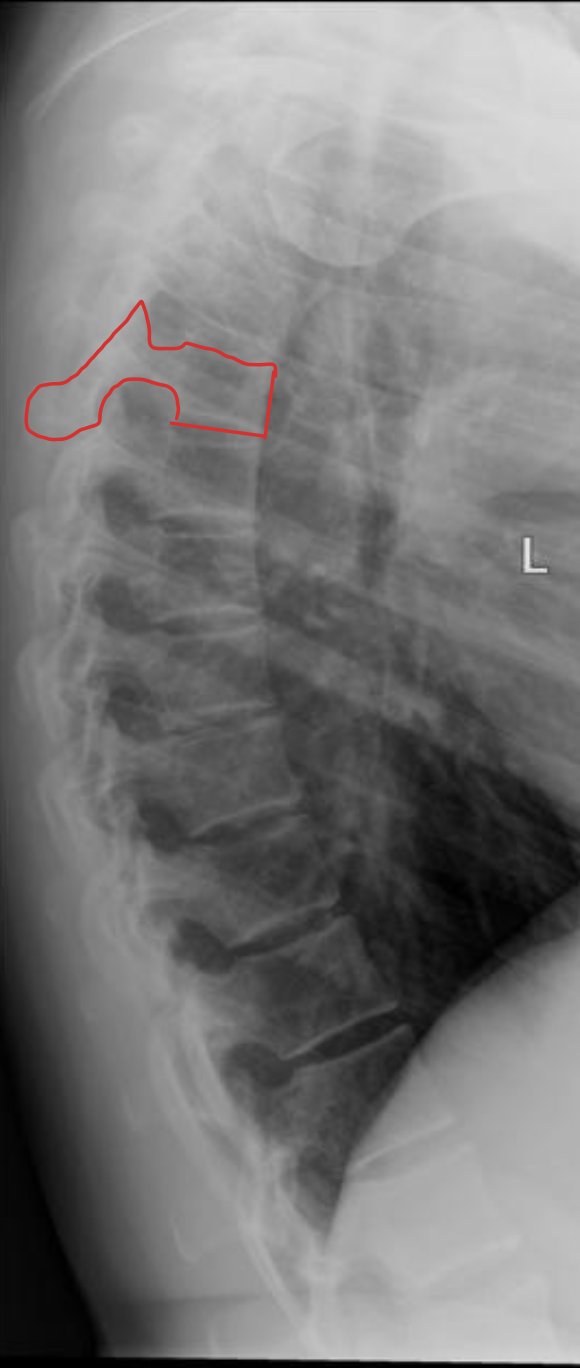

胸椎 12 块

Thoracic vertebrae

胸椎

THORACIC

T1

T2

T3

T4

T5

T6

T7

T8

T9